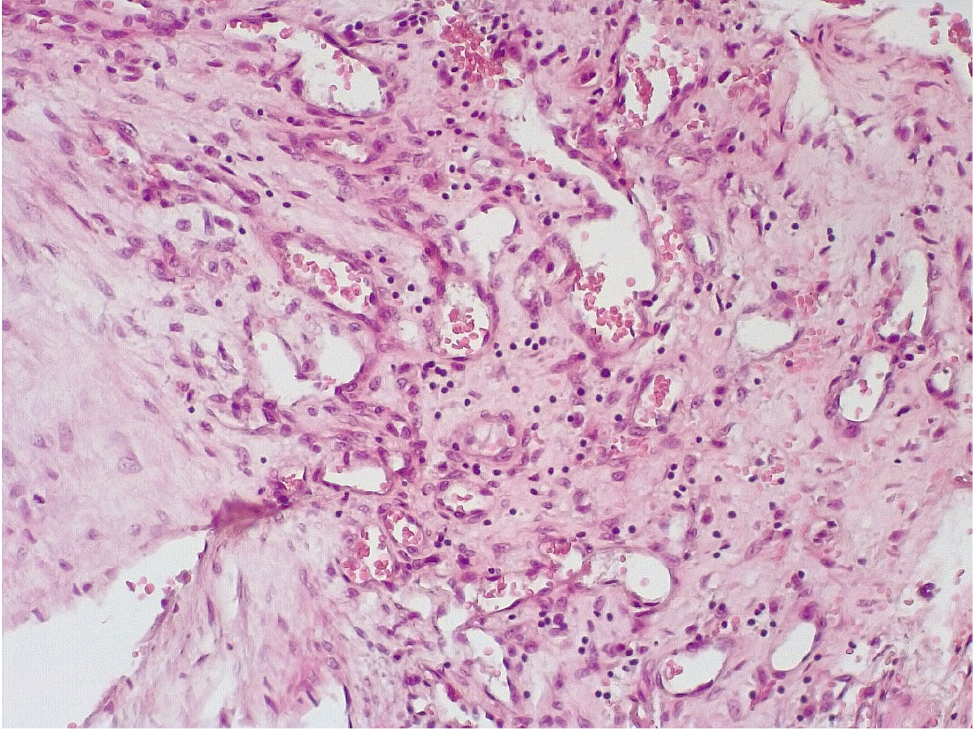

Патоморфологическое исследование стенок КА в ранние сроки после стентирования выявило характерные особенности. В течение первых 3 дней после стентирования в стенке КА имелась атерома с признаками геморрагий. Эндотелий был на большем протяжении разрушен, с признаками десквамации, с окружающей очаговой лейкоцитарной инфильтрацией. Вокруг атеромы, со стороны медии и адвентициальной оболочки, отмечалась умеренновыраженная лимфоцитарная инфильтрация (рис. 1).

В течение 7–15 суток после стентирования КА наряду с формированием пристеночных фибриновых тромбов с признаками организации в стенках атером наблюдались репаративные процессы, связанные с неоангиогенезом в виде образования мелких тонкостенных кровеносных сосудов капиллярного типа, окруженных мелкими лимфоцитарными, гистиоцитарными клеточными инфильтратами (рис. 6, 7).